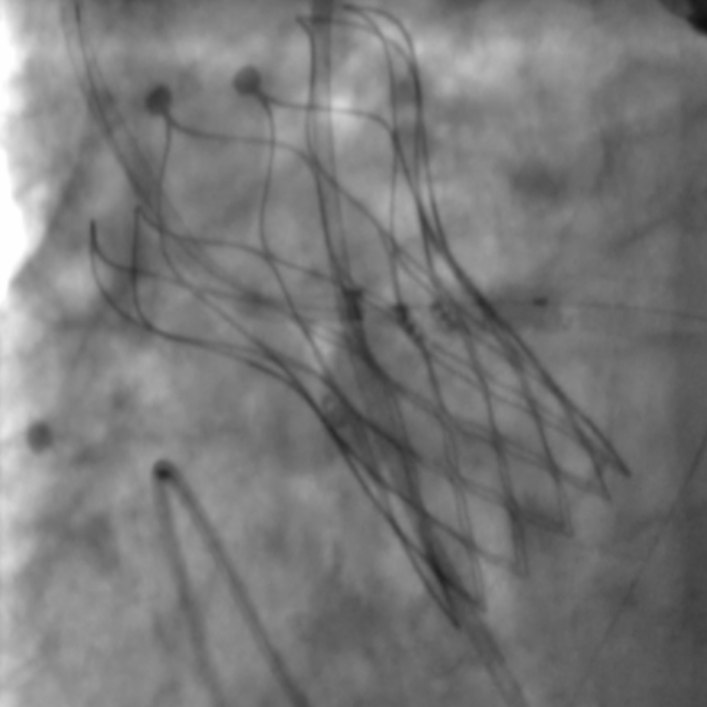

术者团队瓣膜释放中

术后经导管同步测压,跨瓣压差由70mmHg,改善至术后0mmHg。经食道超声显示VitaFlow®瓣膜位置固定,无瓣周漏,瓣膜形态良好。再次通过IVUS评估左侧冠脉开口面积恢复至12.76mm2,患者生命体征平稳并监护。